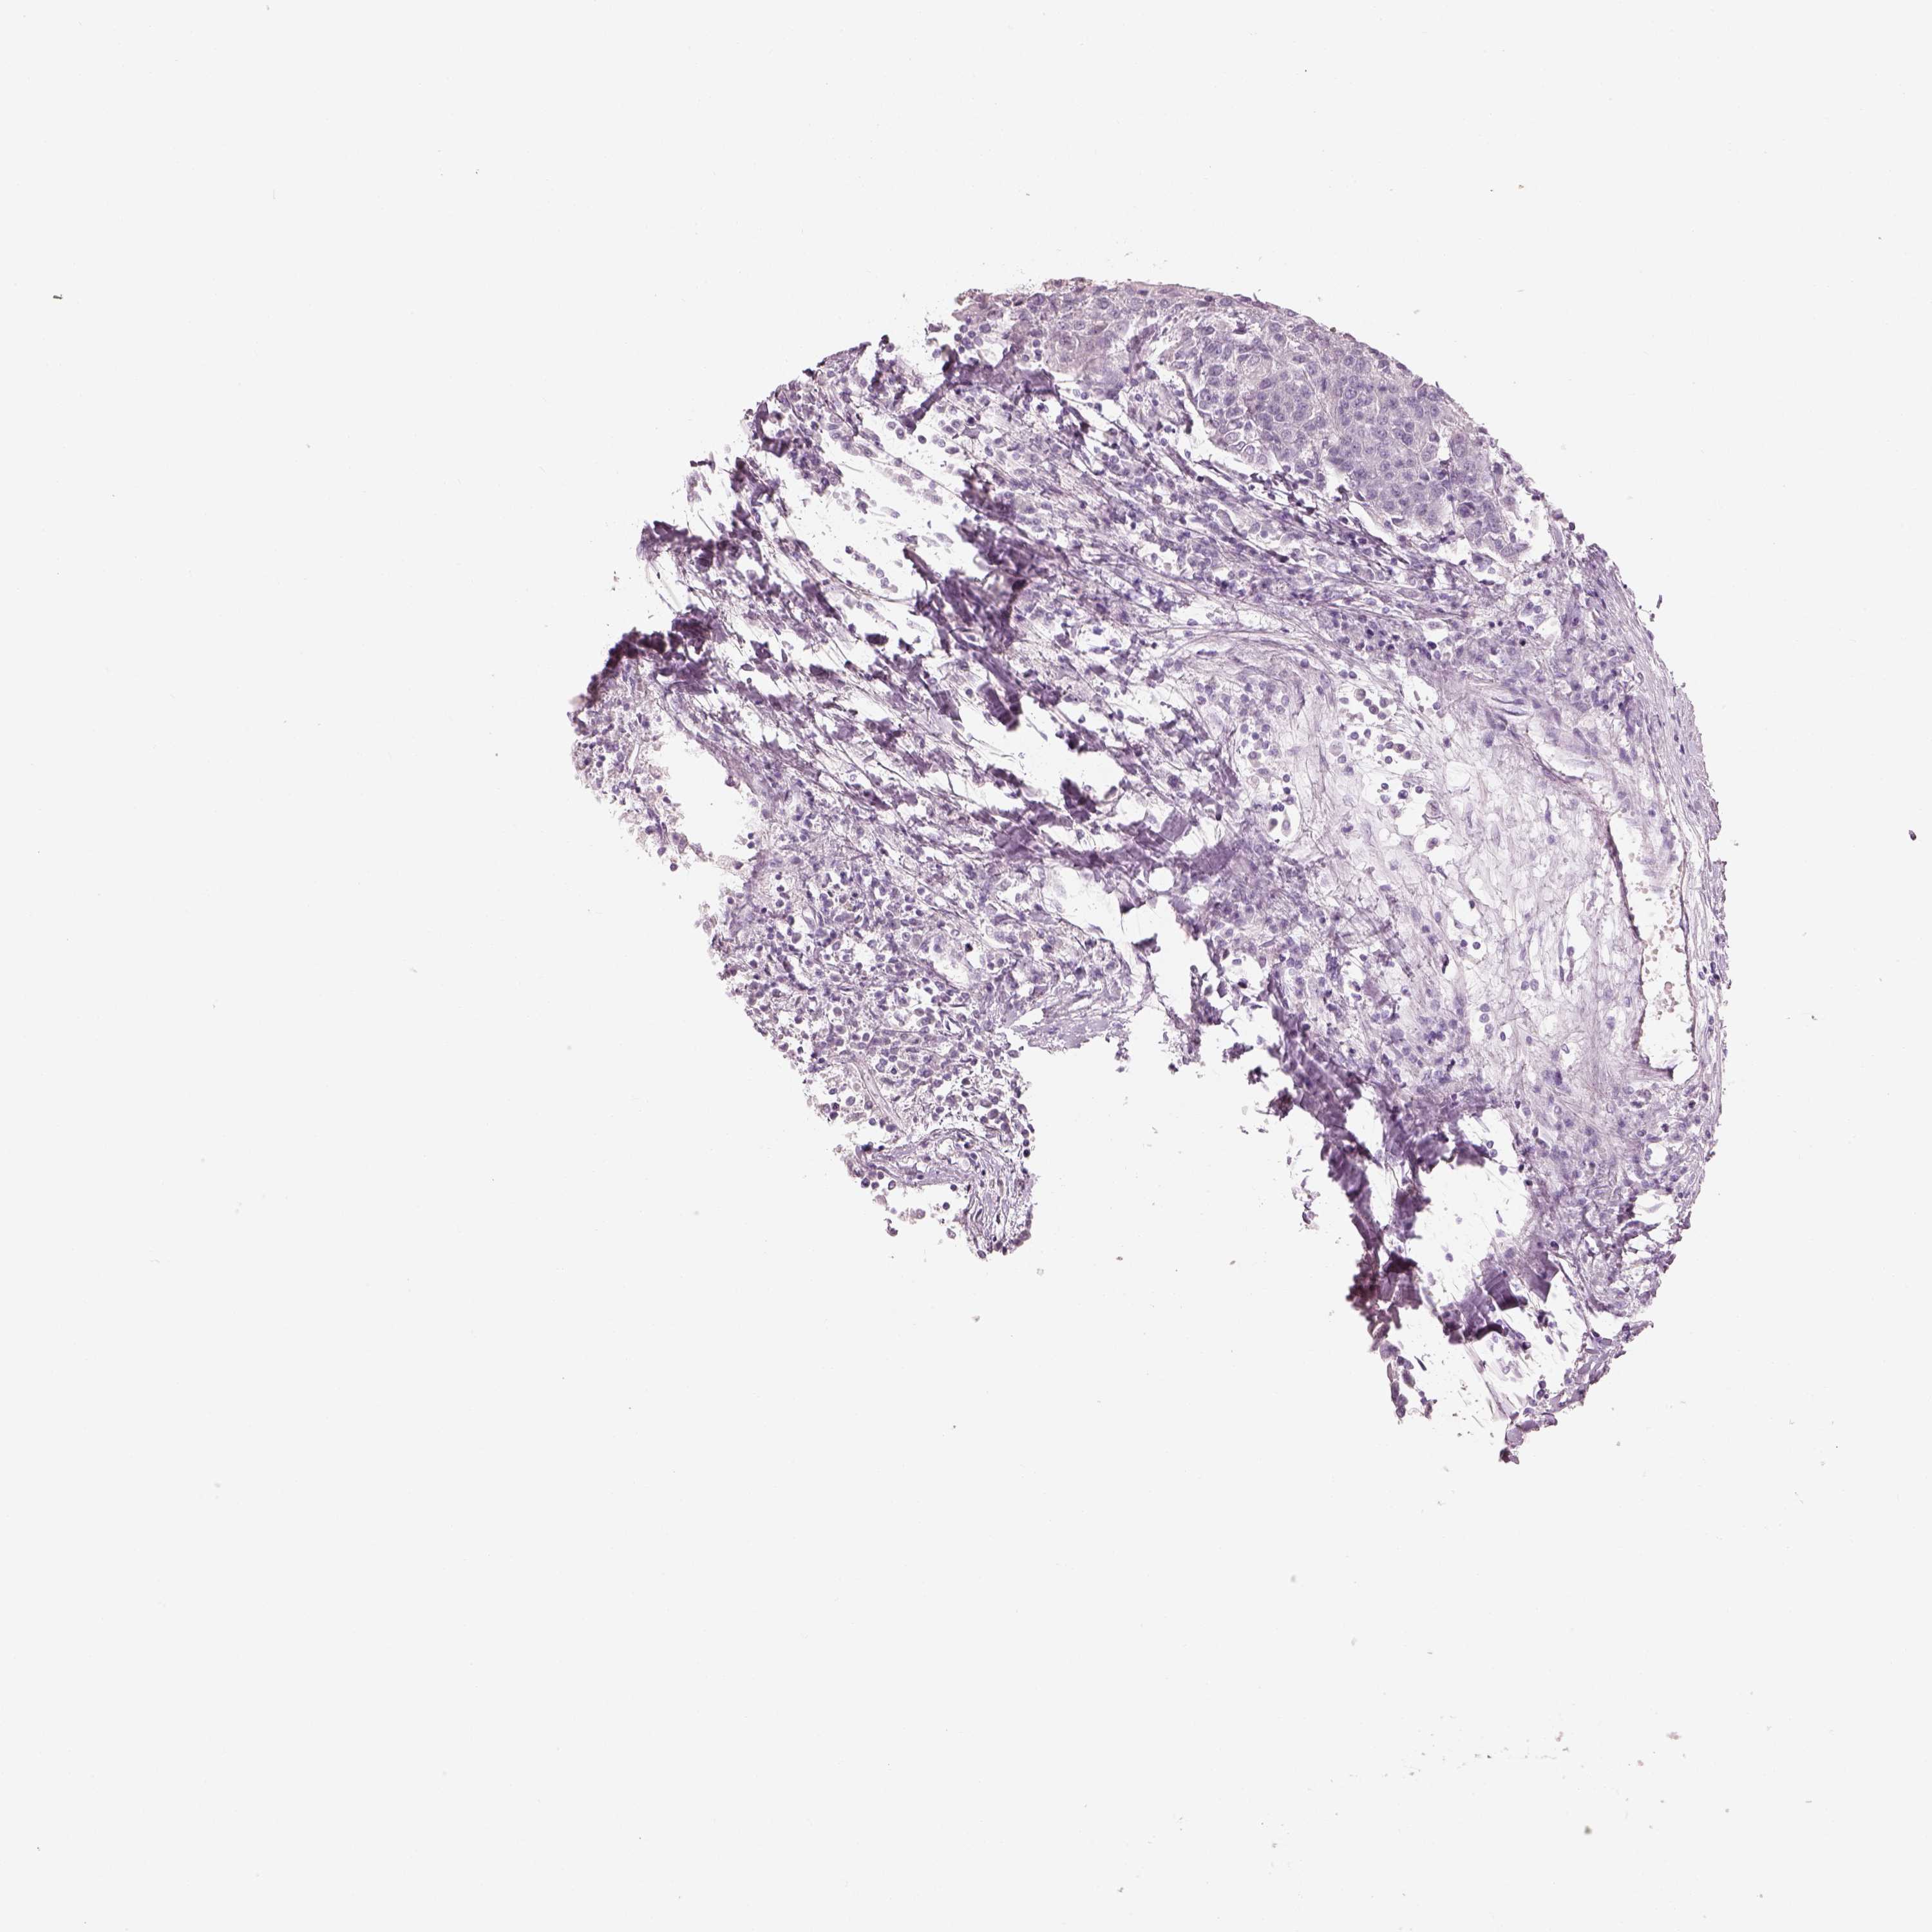

UROTHELIAL CANCER - Protein expressioni

A mouse-over function shows sample information and annotation data. Click on an image to view it in a full screen mode. Samples can be filtered based on level of antibody staining by selecting one or several of the following categories: high, medium, low and not detected. The assay and annotation is described here.

Note that samples used for immunohistochemistry by the Human Protein Atlas do not correspond to samples in the TCGA dataset.

Antibody stainingi

Antibody staining in the annotated cell types in the current human tissue is reported as not detected, low, medium, or high, based on conventional immunohistochemistry profiling in selected tissues. This score is based on the combination of the staining intensity and fraction of stained cells.

Each image is clickable and will lead to virtual microscopy that enables deeper exploration of all samples and also displays staining intensity scores, fraction scores and subcellular localization as well as patient and tissue information for each sample.

Antibody HPA043261

Antibody HPA043264

Antibody HPA044028

Urothelial carcinoma, High grade

Urothelial carcinoma, NOS

Urothelial carcinoma, Low grade